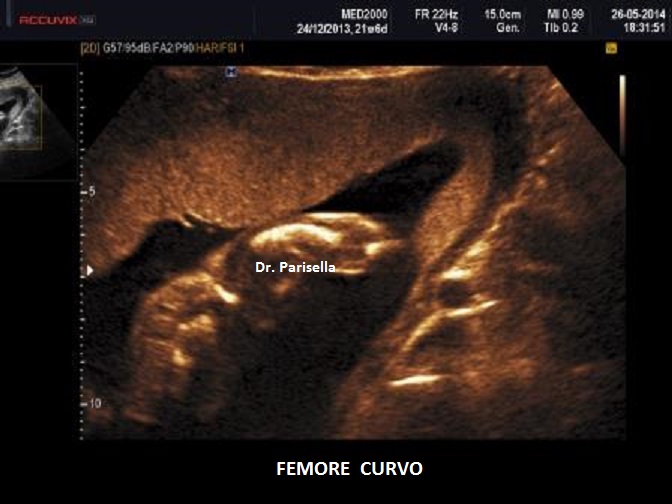

• Displasia scheletrica: ossa lunghe curve, agenesia della fibula, aspetto a ventaglio delle dita dei piedi, polidattilia;